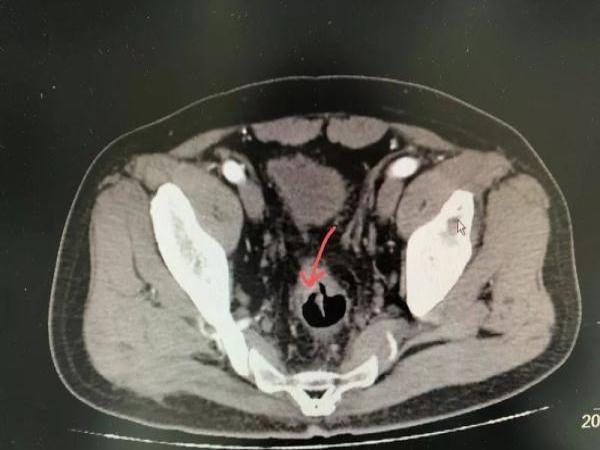

然而 , 今年初开始 , 孙女士常感觉肚子痛 , 最近一个月以来 , 便血的次数越来越多 , 在家人的劝说下 , 她来到医院检查 。 肠镜检查发现 , 直肠上长出新生物 , 经活检检验为直肠腺癌 。

医生介绍说 , 直肠癌早期大多没有症状 , 只会出现腹部胀痛的情况 , 有些患者会因发现便血症状误认为是痔疮发作 。 直肠癌通常多发于四五十岁以上人群 , 近年来 , 因不良生活习惯 , 患结直肠癌的年轻患者比例有所上升 。